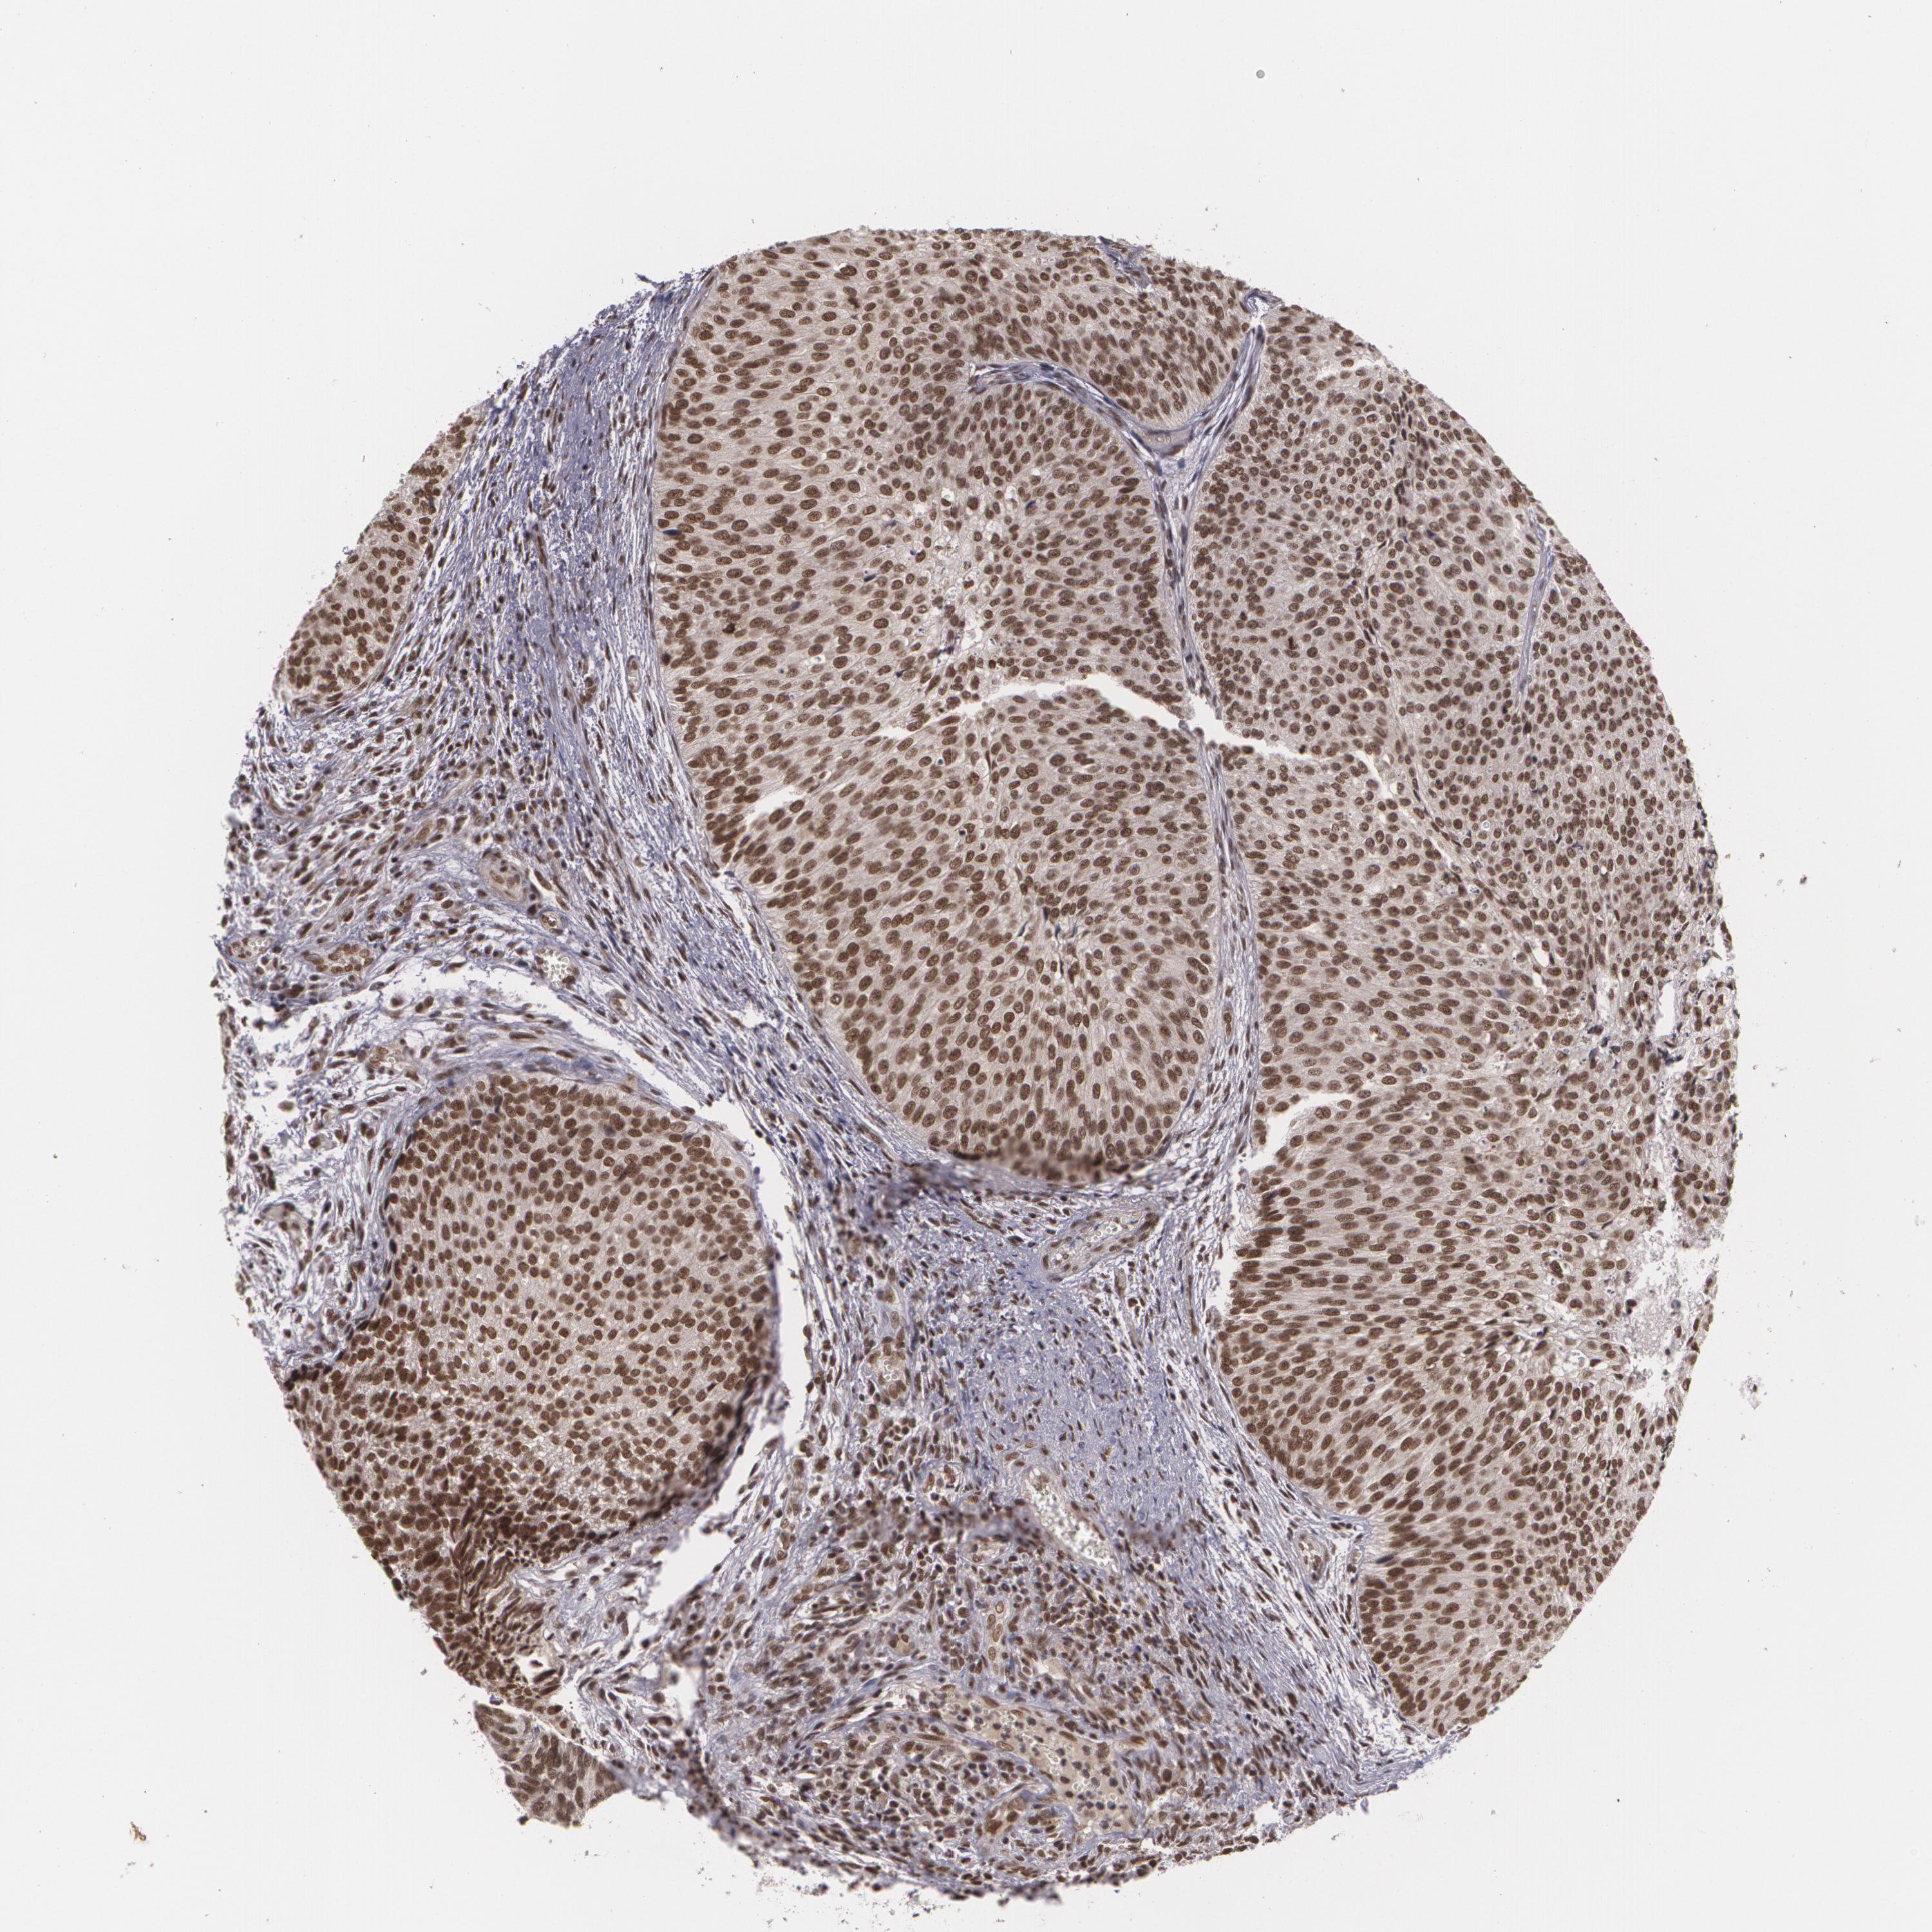

UROTHELIAL CANCER - Protein expressioni

A mouse-over function shows sample information and annotation data. Click on an image to view it in a full screen mode. Samples can be filtered based on level of antibody staining by selecting one or several of the following categories: high, medium, low and not detected. The assay and annotation is described here.

Note that samples used for immunohistochemistry by the Human Protein Atlas do not correspond to samples in the TCGA dataset.

Antibody stainingi

Antibody staining in the annotated cell types in the current human tissue is reported as not detected, low, medium, or high, based on conventional immunohistochemistry profiling in selected tissues. This score is based on the combination of the staining intensity and fraction of stained cells.

Each image is clickable and will lead to virtual microscopy that enables deeper exploration of all samples and also displays staining intensity scores, fraction scores and subcellular localization as well as patient and tissue information for each sample.

Antibody CAB002003

Staining

High

Medium

Low

Not detected

Intensity

Strong

Moderate

Weak

Negative

Quantity

>75%

75%-25%

<25%

None

Location

Nuclear

Cytoplasmic/membranous

Cytoplasmic/membranous,nuclear

Urothelial carcinoma, High grade

Urothelial carcinoma, Low grade

Adenocarcinoma, NOS